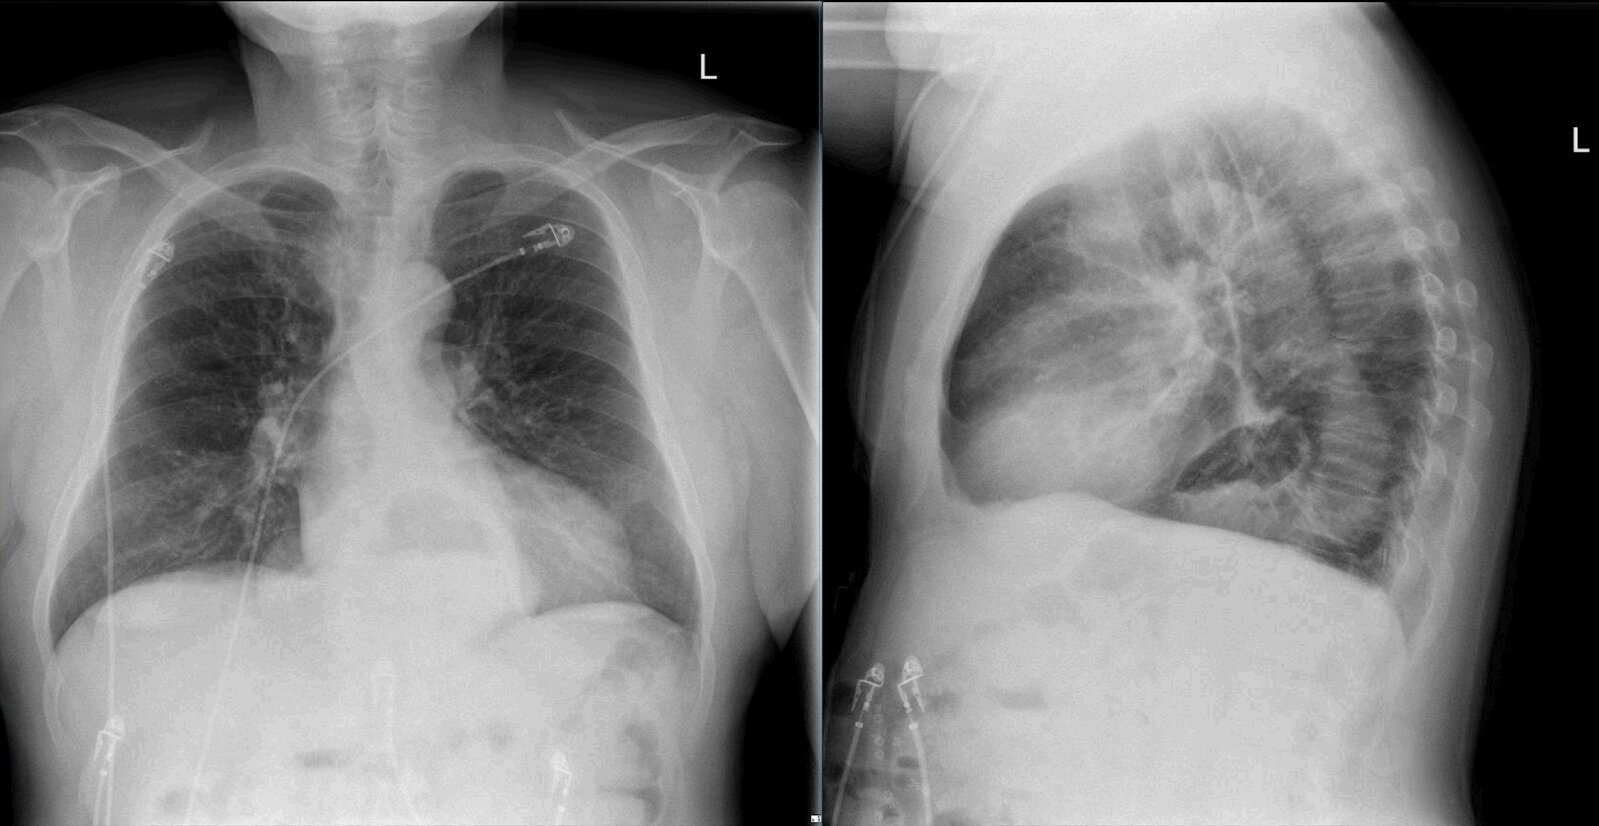

Thoracic aortic aneurysm

• Feeling of pressure in the chest

• Thoracic back pain

• Features of mediastinal compression or obstruction (e.g., difficulty swallowing, hoarseness)

• If ruptured: severe chest pain, possible loss of consciousness

• Chest x-ray: abnormal aortic contour, widened mediastinum, tracheal deviation

• CTA chest: dilation of the aorta, possible mural thrombus, dissection, perforation, or rupture

• See β€œAcute management checklist for thoracic aortic aneurysm.”